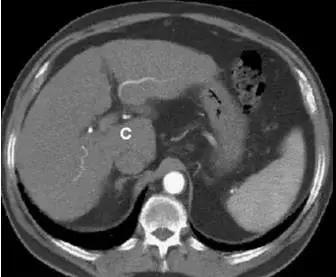

尾状叶:尾状叶(I段)在后方,尾状叶与其他叶不同的是,它经常经静脉直接与下腔静脉,而不通过肝静脉主干,也有可能同时接受门静脉左右支的血供。(下图C)

http://webres.medlive.cn/upload/000/516/238